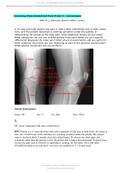

(answered) Assessing Musculoskeletal Pain Week 8 | Assessment; A 15-year-old male reports dull pain in both knees. Latest 2023 - 2024

Assessing Musculoskeletal Pain Week 8 | Assessment Min of 3 reference dated within 5 years A 15-year-old male reports dull pain in both knees. Sometimes one or both knees click, and the patient describes a catching sensation under the patella. In determining the causes of the knee pain, what...